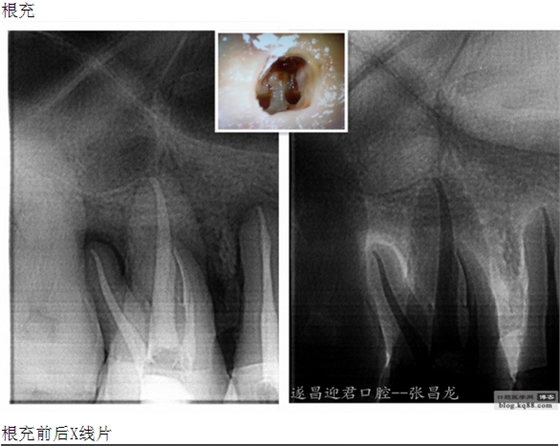

每個牙科醫(yī)生都不愿碰到器械分離,但常在河邊走,哪有不濕鞋的,我想大部分醫(yī)生根管治療中都發(fā)生過器械分離吧。在此就不在累贅那些造成根管器械分離的原因,醫(yī)生們也都知道那些。遇到器械分離莫慌,我們還是有挽救的余地。由于醫(yī)生的技術(shù)原因,設(shè)備原因,不是每個斷針都能取出來的。與對一部分?jǐn)噌樜覀兛梢試L試建立旁路通道,斷針與根管壁之間的間隙慢慢通入到工作長度,然后常規(guī)根管治療。

下面是我最近的一個患者,患者14,15,16均因楔狀缺損導(dǎo)致牙髓壞死,根管治療期間,16的近中頰根發(fā)生了斷針。